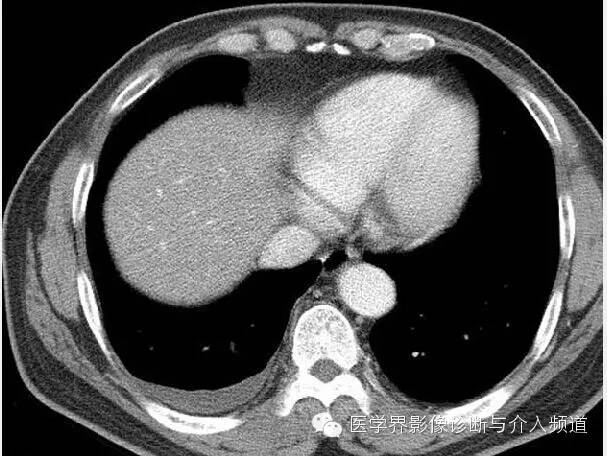

CT显示右肺上叶实性团块病灶内不规则空洞形成,周围可见GGO,右侧胸腔少量积液。患者外周血嗜酸性粒细胞增多和Pw抗体阳性。治疗后X线平片显示右上肺结节影缩小。治疗前X线片显示病灶位于右肺上野,右侧肋膈角变钝。此外,X线平片示主支气管节段性偏心性狭窄,这是由于胸内甲状腺肿外在压迫所造成。